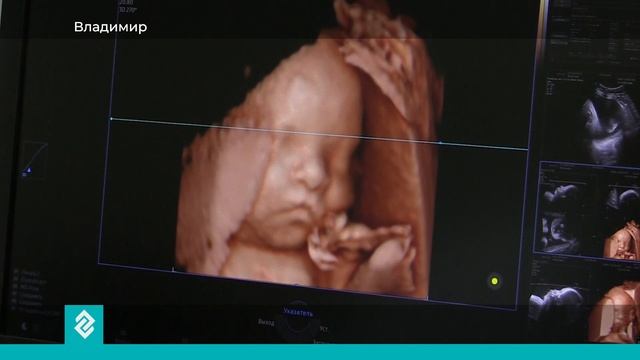

Михаил Николаевич Буланов - заведующий отделением ультразвуковой диагностики Областной клинической больницы, главный внештатный специалист Минздрава. Он работает свыше 40 лет. Работа врача УЗИ - не просто выполнять исследование. Это искусство видеть невидимое. С помощью современной техники доктор не только назовёт пол ребёнка на ранних сроках беременности, но и покажет лицо малыша ещё в утробе матери. После приёма последнего пациента рабочий день не заканчивается. Доктор медицинских наук Михаил Буланов преподаёт онлайн и пишет книги. Он - автор 11 монографий и более 200 научных работ. По стопам отца пошли дети. Сын и дочь тоже стали врачами.